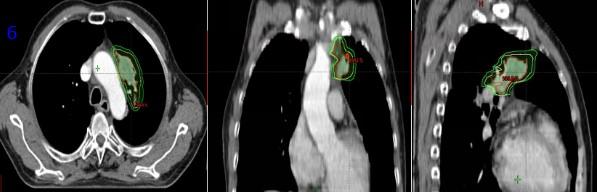

患者于2021-09-06開始放療,腫瘤區(qū)(GTV)劑量PTV6G/30次,計(jì)劃靶區(qū)(PTV)、亞臨床病灶(CTV)劑量50Gy/25次,脊髓:max≤10Gy; 雙肺:V20≤5%;主動脈max≤63Gy(圖6)。期間完成2周期EP方案化療(依托泊苷150ng d1-3+順鉑40mgd1-3),2021.10.20放療結(jié)束。

圖6 放療靶區(qū)范圍(紅線GTV,黃線CTV,綠線PTV)